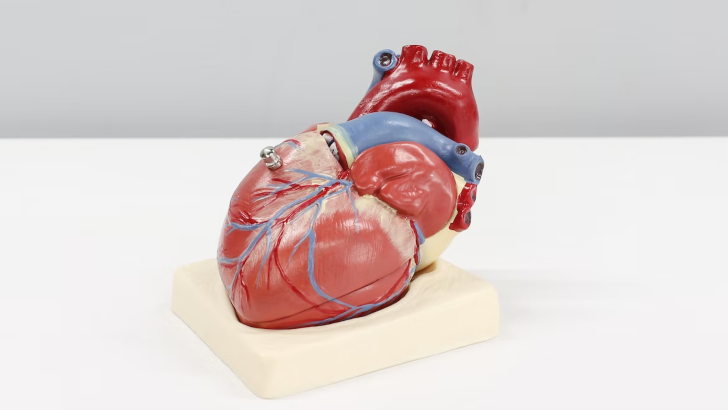

Which of these is true about your heart?

It carries carbon dioxide to your cells

It is a muscle

Your heart is a pump. It’s a muscular organ located slightly left of center in your chest. A lot of the time, people metaphorically think that it contains your emotions, but it doesn’t.

How big is an adult heart that is usually healthy?

The size of a closed fist

The size of a ping pong ball

The size of a closed fist

Your age, body size, and heart health can all affect how big your heart is. The heart can enlarge as a result of some diseases.

Your heart is divided into how many chambers?

4

The right and left atria are the heart’s upper chambers. The heart also has two lower chambers (the right and left ventricles). The left side of your heart receives oxygen-rich blood from the lungs and sends it through the aorta to the rest of your body. The right side of your heart pumps oxygen-poor blood to your lungs.